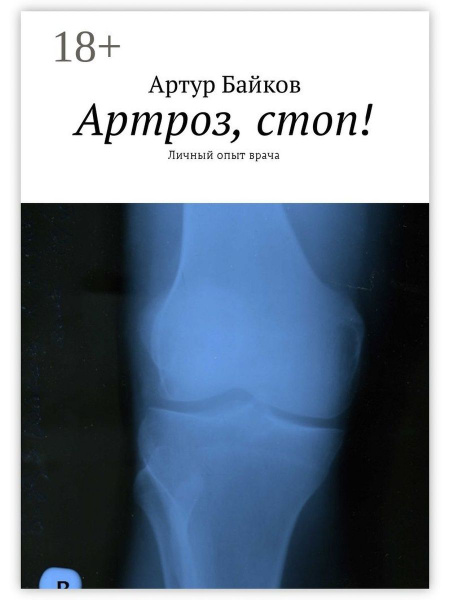

Гитт артроз

Гитт артроз 104 фотографий